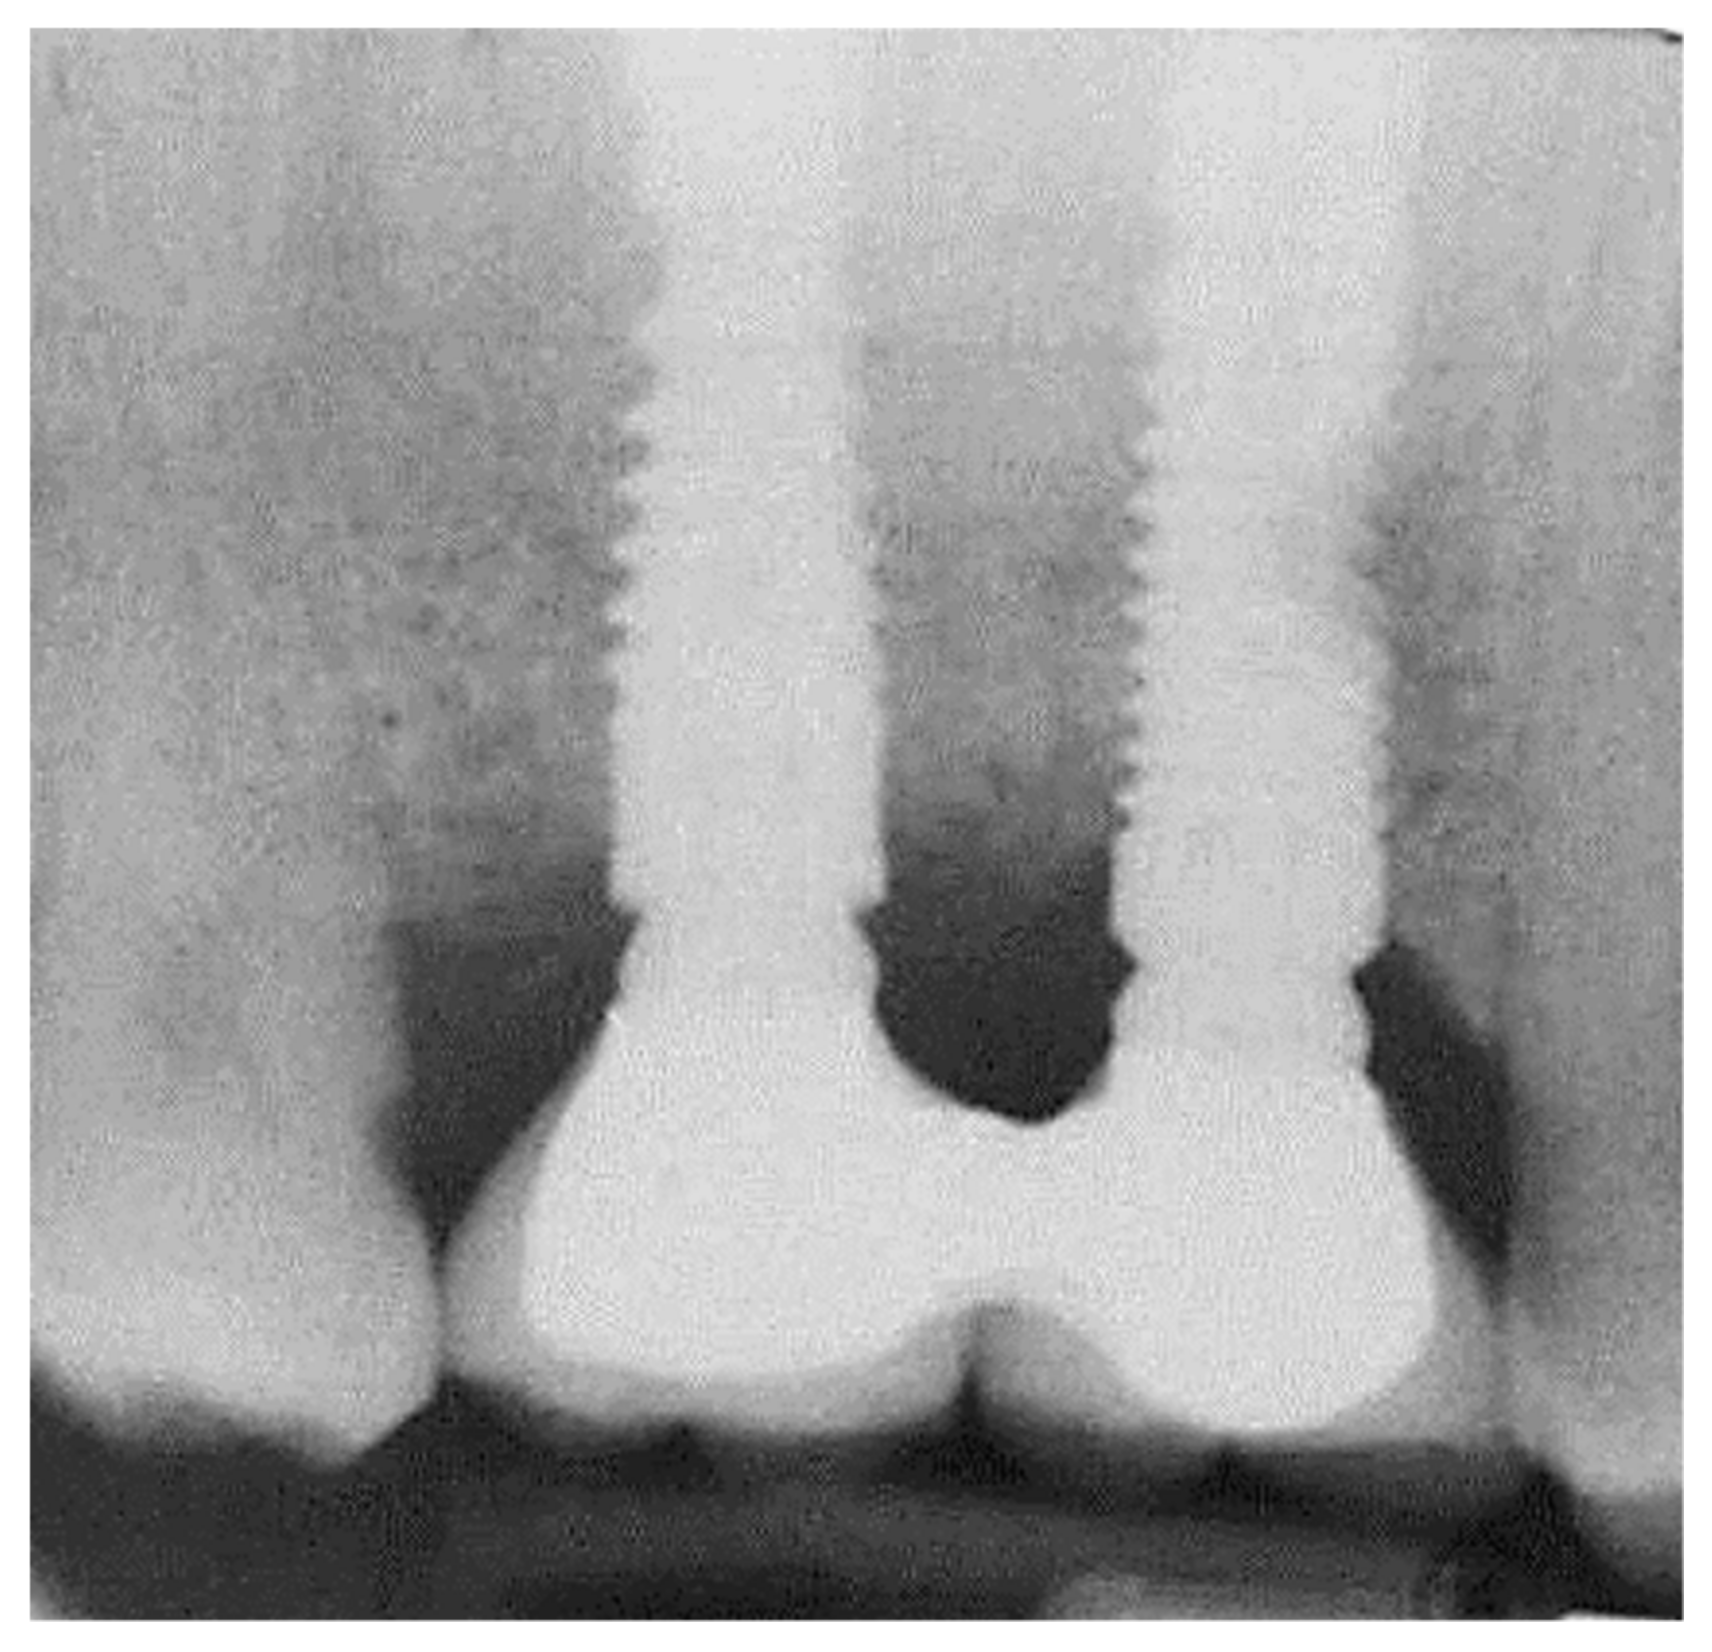

2.2. Marginal Bone Loss